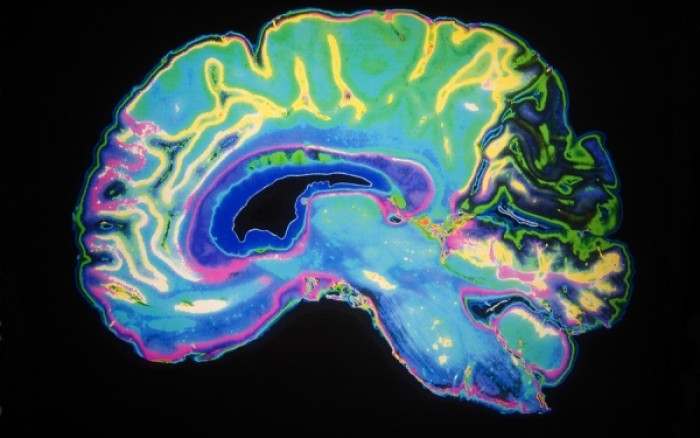

Αλτσχάιμερ: Ο εγκέφαλος «αντισταθμίζει» τις πρώιμες βλάβες

Ο ανθρώπινος εγκέφαλος είναι σε θέση να αποκαταστήσει εν μέρει πρώιμες μεταβολές που οφείλονται στη νόσο Αλτσχάιμερ, σύμφωνα με νέα μελέτη που δημοσιεύεται στην επιθεώρηση Nature Neuroscience. Τα ευρήματα της μελέτης υποδεικνύουν ότι σε ορισμένες περιπτώσεις ο εγκέφαλος έχει την ικανότητα να «επιστρατεύει» περισσότερους νευρώνες ώστε να διατηρεί τη νοητική λειτουργικότητα. Οι ερευνητές ευελπιστούν πως η ανακάλυψη αυτή θα τους βοηθήσει να κατανοήσουν καλύτερα γιατί κάποια άτομα που εκδηλώνουν πρώιμα σημάδια Αλτσχάιμερ παρουσιάζουν στη συνέχεια σοβαρά προβλήματα μνήμης. Η νέα μελέτη, με ερευνητές από το Πανεπιστήμιο της Καλιφόρνια επικεφαλής,...